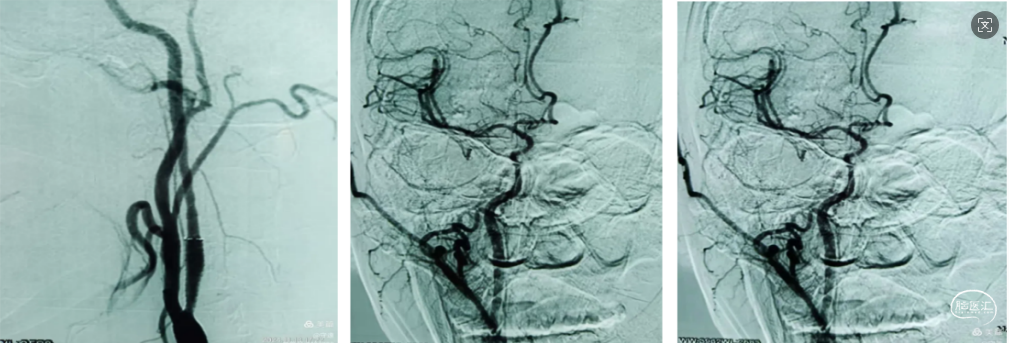

造影示:左侧颈内动脉起始部以远未向远端供血,左侧颈总动脉呈火苗样窜动。查询颈内动脉造影颈内动脉血流火苗样迟滞窜动。

8Fguiding到达C1段支撑070银蛇中间导管裸奔边上行边抽吸,抽出部分血栓,造影显示到血流达到C6段。

术中边推进导管边抽吸,抽出部分血栓,造影显示到血流达到C6段。

支架取栓:

1、微导管到位:微导丝通过M1段艰涩困难,再次偿试通过M1段到达M2。携带微导管到达M2段,微导管造影显示远端有正向血流,在真腔内。下图1

2、支架释放:通过027微导管释放6X30mm 通桥蛟龙支架,静置5分钟后微造影,大脑中未显影,未见首过效应考虑血栓负荷较大。大脑前有血流。下图2

4、中间导管收拢支架尾部一体回撤:中间导管跟进至M1段收拢支架尾部下,负压踹马桶抽吸中间导管,缓慢一体回撤支架和中间导管,一次取出长约3.5cm黯红色血栓。

造影显示:

大脑中动脉畅通,远端血流达3级。但分叉以远分支似有少量血栓。考虑6x30m支架放置M2段过大,未再进行远端分支取栓,经导引导管给予替罗非班6ml推注。结束手术。